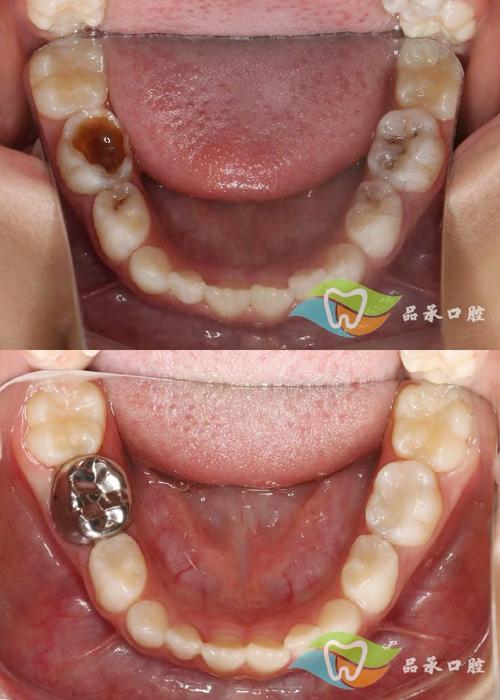

- 病灶牙处理:植入区域有残根、残冠或严重龋坏牙,需先拔除或根管治疗,避免术后感染源扩散。